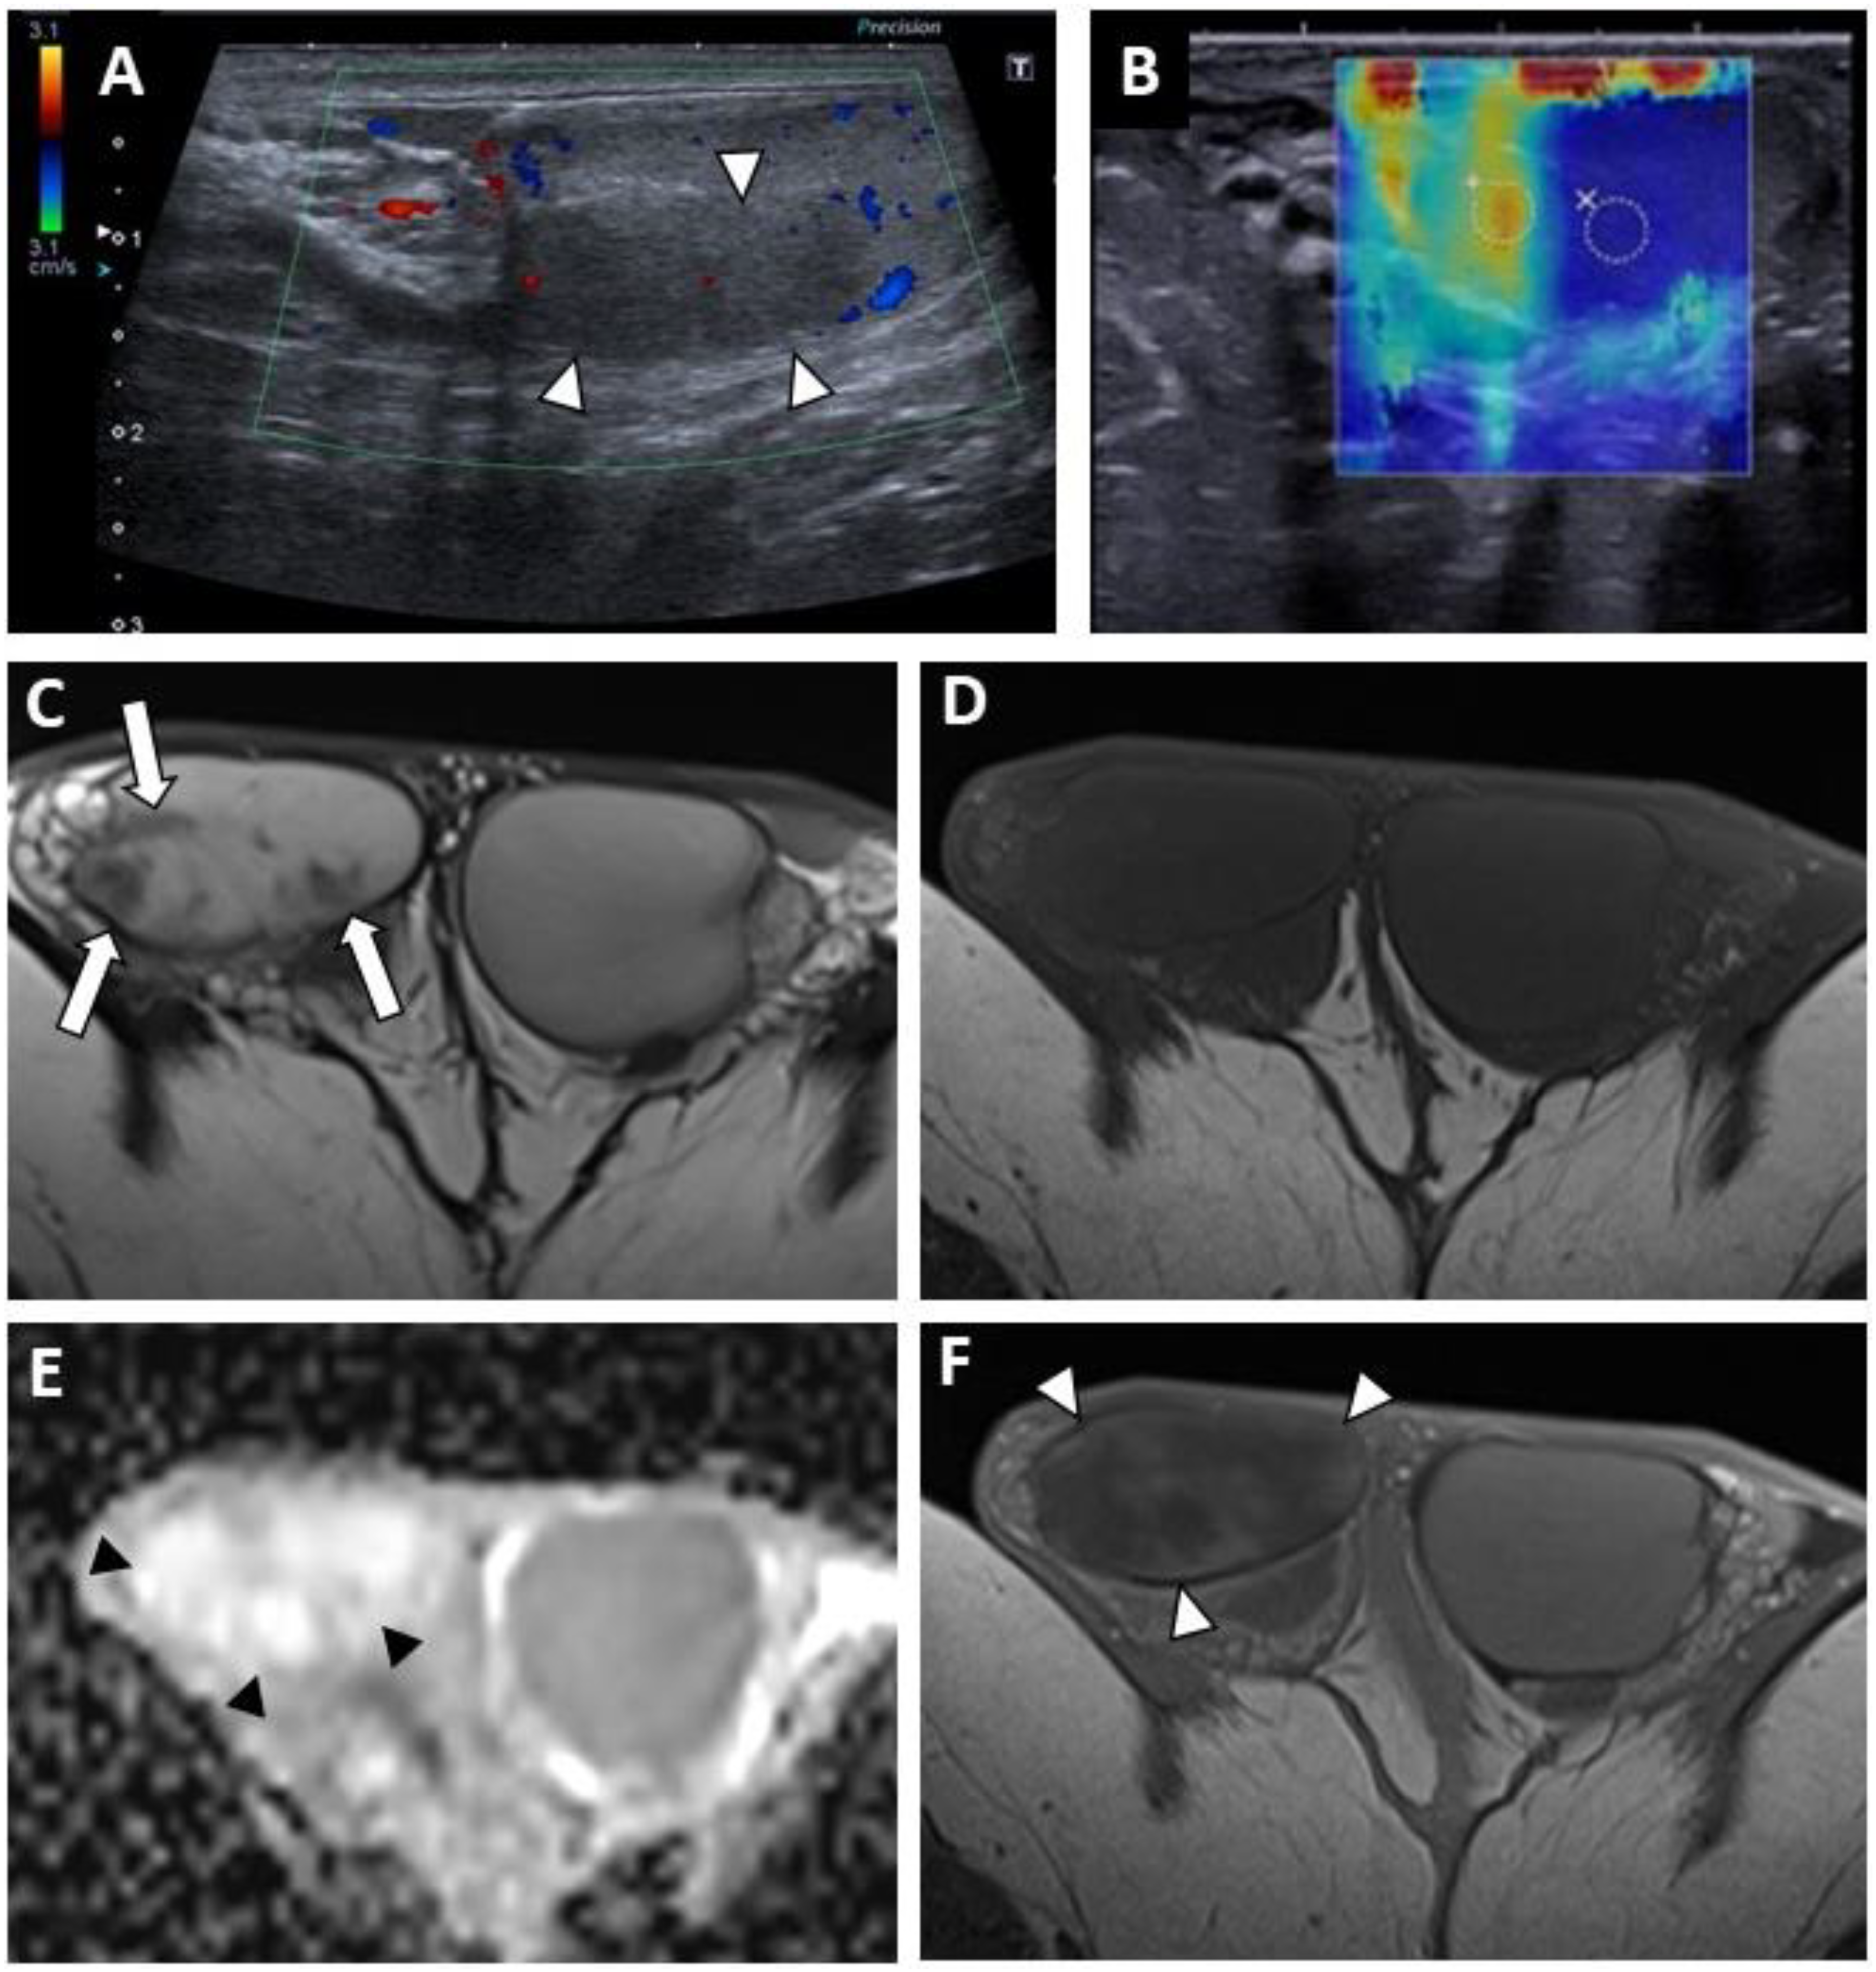

3.2.1. Conventional US Findings

3.2.2. MRI Findings

| Lesion pattern | ||||

| - Nodular area | 22 (84.6) | 11 (100) | 10 (90.9) | 44 (91.7) |

| - Entire testis infiltration | 4 (15.4) | 0 | 1 (9.1) | 4 (8.3) |

| - ill-delineated | 26 (100) | 11 (100) | 11 (100) | 48 (100) |

| Echogenicity | ||||

| - Hypoechoic | 25 (100) | 11 (100) | 11 (100) | 48 (100) |

| Maximal diameter * (SD) (mm) | 13 (4.4) | 13.5 (5.2) | 14.1 (4.5) | 13.1 (4.5) |

| Vascularization | ||||

| - Hypovascular | 20 (76.9) | 11 (100) | 11 (100) | 42 (87.5) |

| - Hypovascular area with hypervascular focal nodule | 6 (23.1) | 0 | 0 | 6 (12.5) |

| Microlithiasis (random MLs) | ||||

| - <5 per FoV | 3 (11.5) | 1 (9.1) | 4 (36.4) | 8 (16.7) |

| - >5 per FoV | 2 (7.7) | 0 | 0 | 2 (4.2) |

| - diffuse | 2 (7.7) | 0 | 0 | 3 (6.3) |

| - Clustered microliths | 15 (57.7) | 8 (72.7) | 6 (54.5) | 29 (60.4) |

| Macrocalcifications | 5 (19.2) | 5 (45.5) | 7 (63.6) | 17 (35.4) |